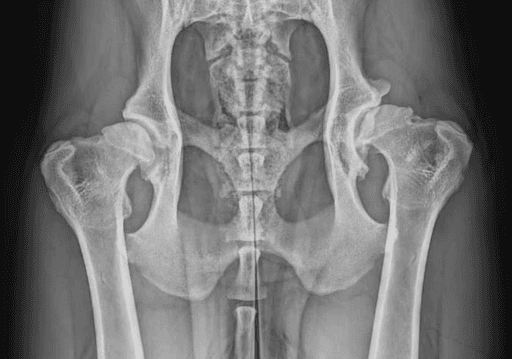

Canine Hip Dysplasia (CHD) is one of the most common causes of hindlimb lameness in dogs,

with genetics playing a major role in its development. The condition begins during early growth when there is laxity (looseness) in the hip joint.

Normally, the femoral head (ball) fits snugly within the acetabulum (socket), allowing smooth motion and even joint development. When the joint is too loose, abnormal forces lead to uneven growth of the bones, stretching of the joint capsule, asymmetric cartilage wear, and bone remodeling. Over time, these changes result in cartilage loss, scar tissue formation, and the development of bone spurs (osteophytes).

Diagnosis involves a combination of history, physical examination, and pelvic X-rays.

In young dogs, hip laxity can be detected with an Ortolani test, though false negatives can occur. As dogs mature, this test becomes harder to elicit and often requires sedation. Standard X-rays are the most common tool to identify hip dysplasia, but visible changes may not appear until a dog is over a year old. The PennHIP distraction x-ray view, performed under sedation, provides the most accurate early detection of hip laxity and can be done as early as 4 months of age.